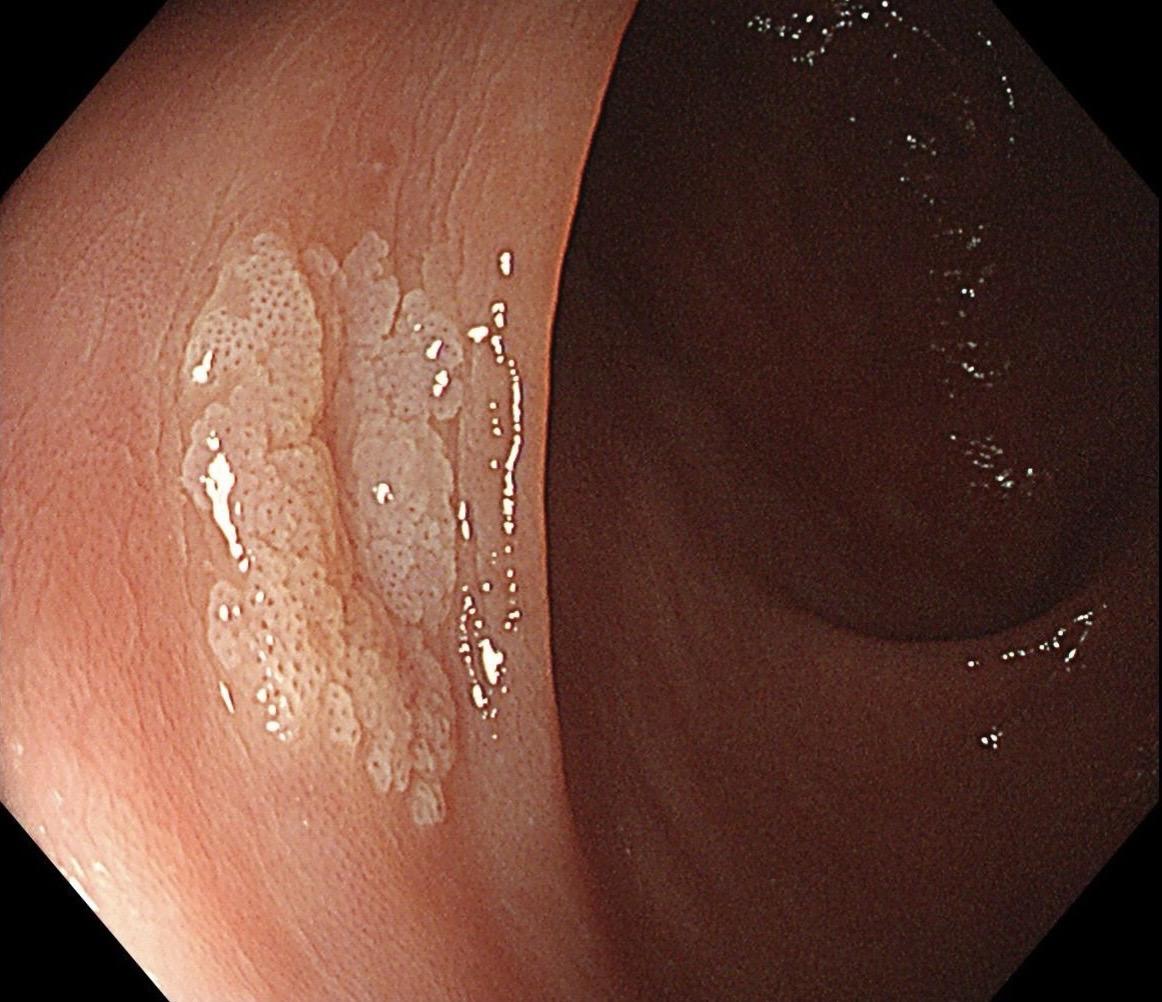

结肠SSL 醋酸染色。染色效果不亚于靛胭脂,结合NBI,Near focus观察表面结构非常OK,下次让护士长买大桶装的,1桶6块9,可以喷一年,哈哈……

结肠SSL 醋酸染色。染色效果不亚于靛胭脂,结合NBI,Near fo...